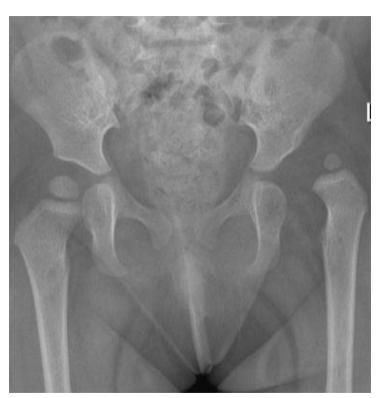

A teenager with acute onset of pain in the right hip during a run. He sustained the injury seen in the x-rays with a white arrow. This injury usually occurs due to a forceful eccentric contraction of which of the following muscles?

- C. Rectus femoris

- Sartorius

Which of the following muscles is attached to the structure pointed by the arrow?

- C. Sartorius

Note: Arrow was pointing at ASIS (Anterior Superior Iliac Spine)